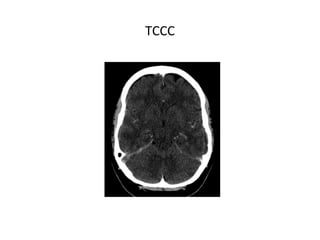

TCCC

TC

• TC CON CONTRASTE IV

SIGNOS DIRECTOS

- Signo del delta vacío: es el signo directo más frecuente, se

observa hasta en un 30% de los casos.

- Ectasia venosa.

SIGNOS INDIRECTOS

- Realce tentorial.

- Realce giral.

- Realce parenquimatoso.